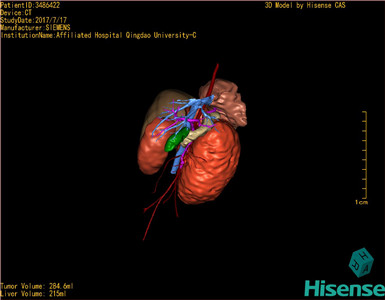

CT结果输入海信CAS系统后行3D重建及手术规划后,于2017-7-21全麻下行“左肾切除术”手术治疗:

术前三维重建及手术方案设计:

将0.625mm双源薄层CT资料的静脉期和动脉期Dicom格式文件导入海信CAS系统。

通过调节窗宽窗位调整CT序号,对肿瘤,肝实质,胆囊,下腔静脉,肿瘤,肝动脉、门静脉及肝静脉等进行三维重建;系统自动计算肿瘤体积和肝脏体积。

模拟手术操作,自动计算切除肿瘤体积。肝脏体积为215ml,肾脏肿瘤大小为284.6ml通过术前模拟手术,精准判断手术可行性。

术前三维重建:

重建图片